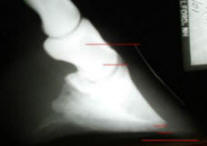

Aside

from the rotation, notice the calcification of the lateral cartilages

and osteophytes at the joints. |

6 months

later, the attending vet was quick to point out that the "derotation"

and the soundness of this horse were not nearly as important as the

speed at which the body is absorbing the calcifications. |

Immobile at start, pasture

sound in about one month; 6 months later, he's being comfortably ridden

daily on all terrain. It is very important to note how much larger the

"impact zone" behind P3 has become. Sound, heel-first impact is

developing the lateral cartilages.

I still hope for the coronet to migrate further

down P3 and am curious about whether the calcifications will continue to

disappear, so again, I'll post updated radiographs in 6 more months.